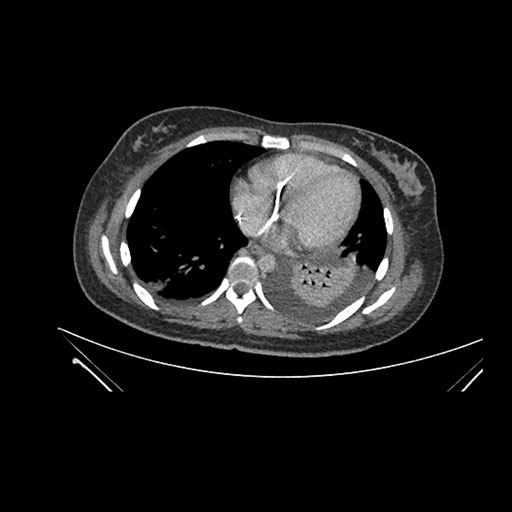

Imaging Analysis

Look through the patient's CT scan to identify any areas of concern for the necessary procedure.

Axial Arterial

Based on initial findings, which issue(s) would you be most concerned about?